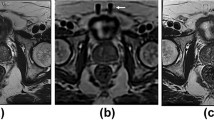

This study aimed to assess the clinical feasibility of employing synthetic diffusion-weighted (DW) images with different b values (50, 400, 800 s/mm2) for the prostate cancer patients with the help of three models, namely CycleGAN, Pix2PiX, and DC2Anet. DW images of 170 prostate cancer patients were used to train and test models. Here, 119 patients were assigned to the training set and 51 patients to the testing set according to a ratio of 7:3. To generate synthetic b value DW images based on CycleGAN, Pix2Pix, and DC2Anet networks, three experiments were performed as follows: generating synthetic DW images with b values of 400 and 800 s/mm2 from acquired DW images with b value of 50 s/mm2; generating synthetic DW images with b value of 800 8 s/mm2 from acquired DW images with b value of 400 s/mm2. Five metrics were used to compare real and synthetic b values. These metrics included Mean Absolute Error (MAE), Root Mean Squared Error (RMSE), Pearson’s Correlation Coefficient (PCC), Peak-Signal-to-Noise-Ratio (PSNR), and Structural Similarity Index Measure (SSIM). As well as, ADC values for different b values were computed using the mono-exponentially mode. The whole prostate volume was manually segmented by drawing regions of interest (ROIs) in each slice of the ADC maps. P values less than 0.05 were considered statistically significant. Based on the quantitative evaluation and for all metrics, especially for generating b values of 400 and 800 s/mm2 from a b value of 50 s/mm2, the DC2Anet model was found accurate and it outperformed CycleGAN and Pix2Pix models (P < 0.05). It is necessary to mention that the agreement between synthetic ADC (sADC) and real ADC (rADC) was satisfactory. No significant difference was observed in the one-way ANOVA between sADC and rADC in the whole prostate volume (P > 0.05). Our results showed the significant potential of the three used models for generating images with different b values in the case of prostate cancer. The results demonstrated that the used three models were accurate and robust for generating DW images and also, they outperformed other methods mentioned in the literature review.